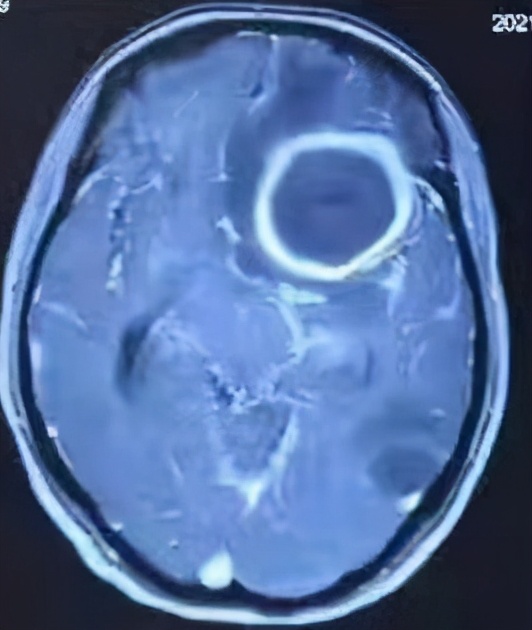

患者为一23岁青年女性,因头痛10天,加重伴发热、恶心2天入院,入院时精神萎靡,体重仅35公斤。头颅MRI检查后发现患者为重症颅内感染,继发形成2个脑脓肿,大脑深部较大者43mmx50mmx37mm,脓肿量约40ml,较小者26mmx23mmx24mm,脓肿量约7ml,严重压迫周围脑组织(图1),随时有脑脓肿破裂和脑疝发生风险,严重危及生命。同时检查发现患还有先天性完全性心内膜垫缺损,属于严重的较少见心脏病,合并3级心力衰竭、肺动脉高压、重度营养不良,病情十分危急。

图1